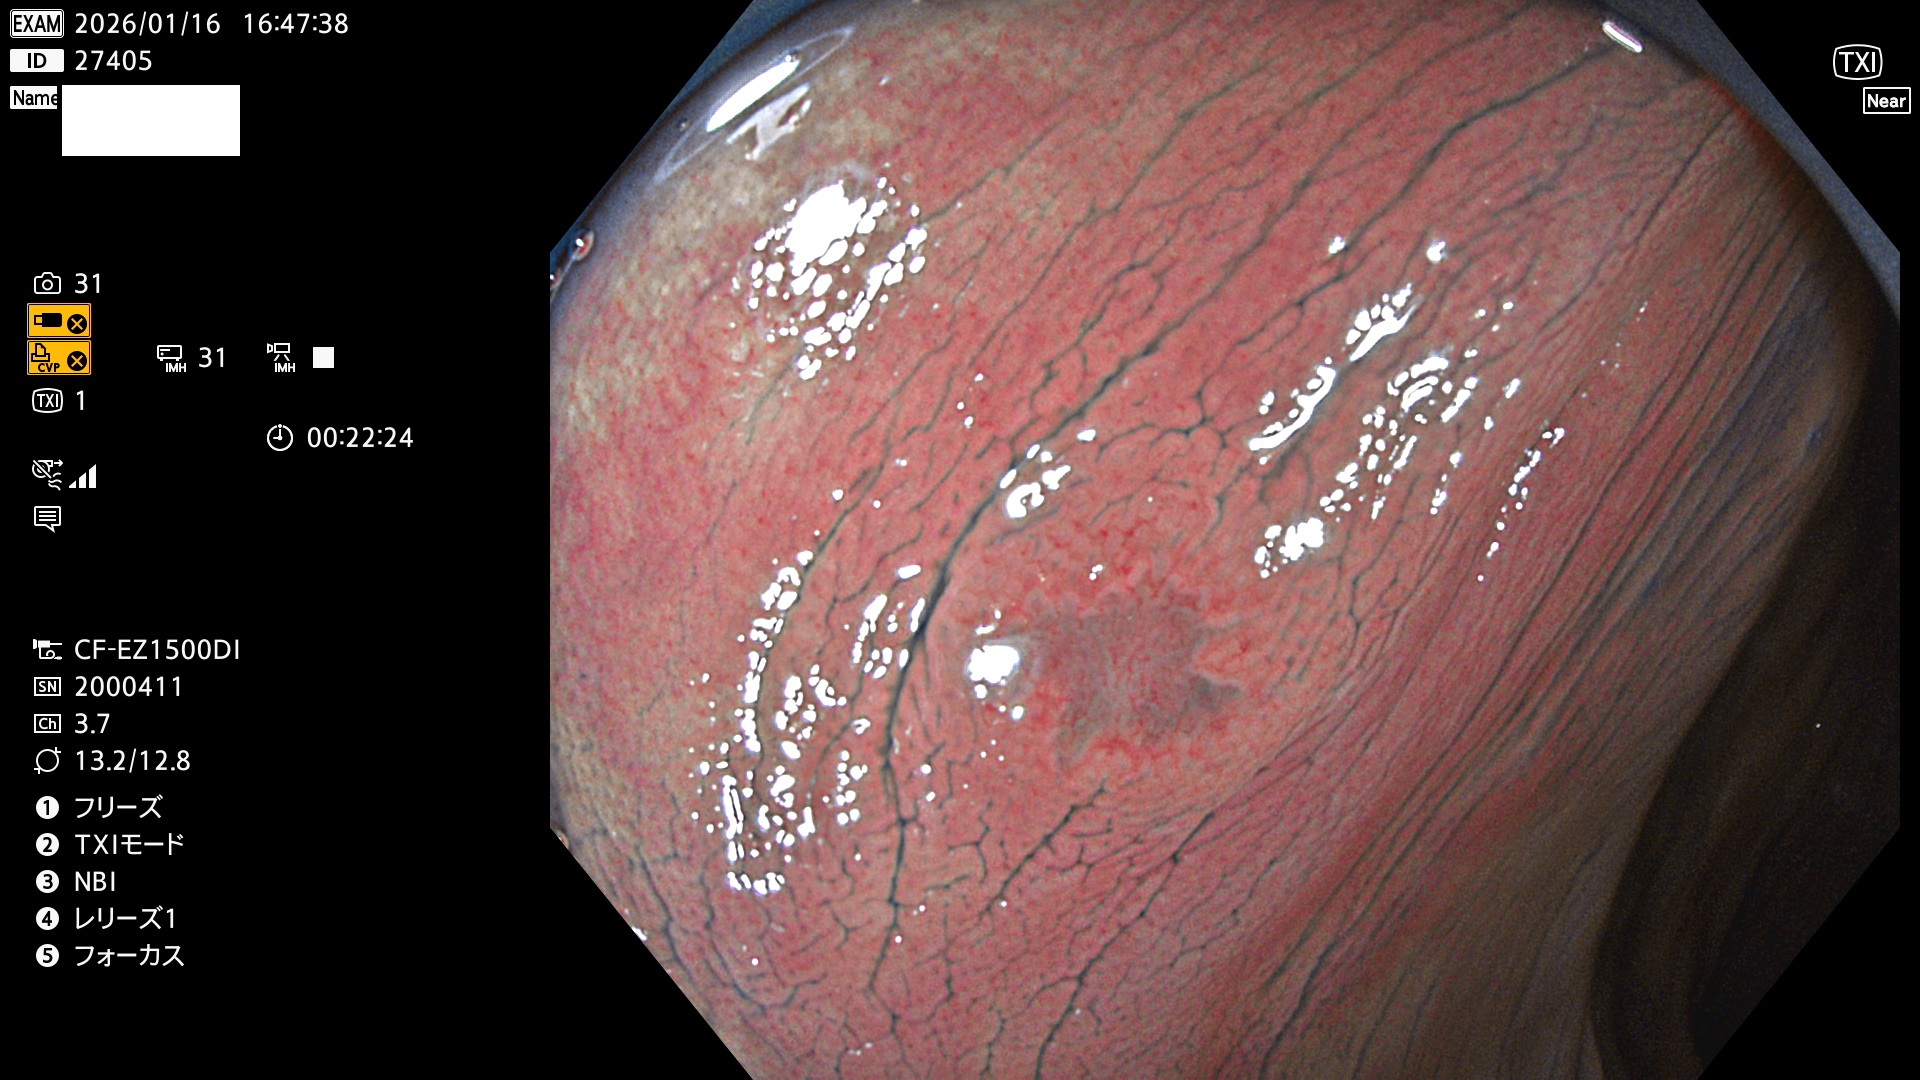

完全に平坦な物をUb、陥凹している物をUcと呼びます。Ubは認識が困難で、Ucはびらん(炎症)と紛らわしいために見落とされやすく、「内視鏡後・大腸癌」の原因になります。

2026年1月15日〜1月18日の4日間(40件)で5個 (Uc_ADR=5個/40人=13%)